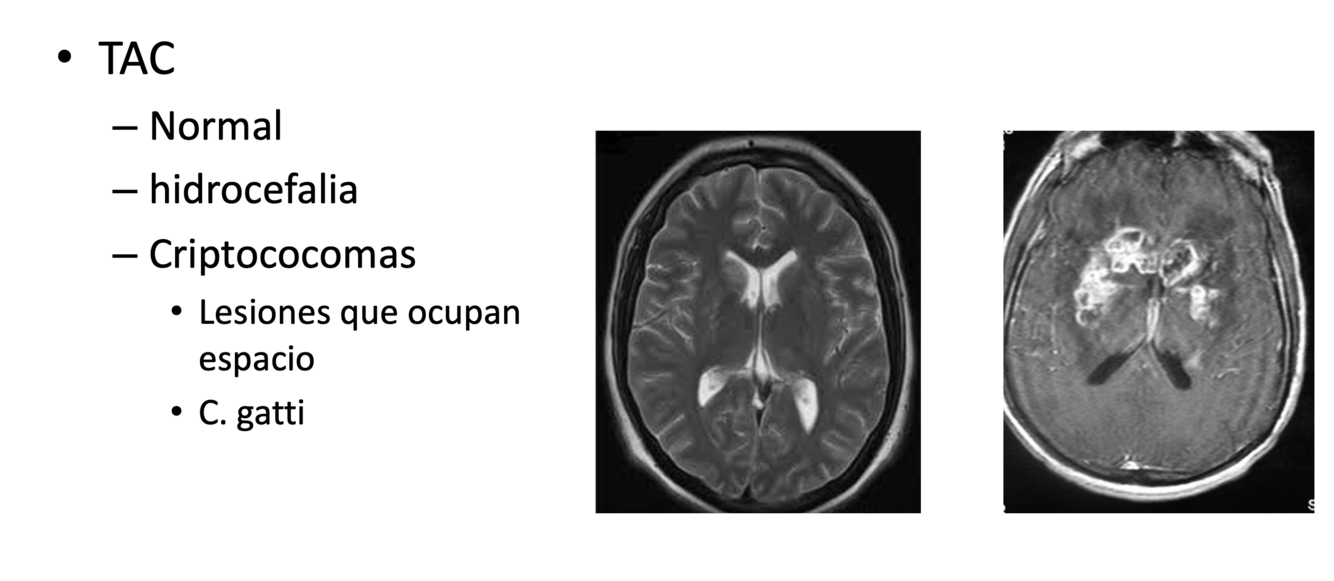

Imagen

A

CRIPTOCOCOMAS: más asoc personas sanas